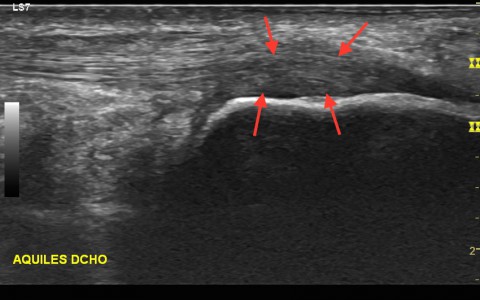

La aplicación de la técnica EPI, consistirá pues en una aplicación de un tipo concreto de electroterapia Galvánica continua con un aguja mediante control eco-guiado para producir una respuesta inflamatoria del tejido degenerado e inducir a su proceso de reparación fisiológico, favoreciendo así la reparación del tejido blando afectado. Ya en 1996, Balcavage et al. observaron que la corriente eléctrica inducida en el tejido a frecuencias bajas (50-60 Hz) tiene un efecto directo sobre la membrana celular.

La técnica EPI® consiste en un primer lugar en realizar una recogida de datos del deportista e historia de su lesión, mediante ecografía músculo-esquelética se realizará un estudio para ver el origen de la lesión, diferenciando ensopatías, tendinopatias, fibrosis y roturas musculares. Creando un protocolo personal con diferentes técnicas y ejercicios dirigidos por un Fisioterapeuta . En muchas ocasiones el ejercicio debe ser corregido mediante vendaje, tipo MaCconnell para la corrección de la alineación rotuliana, y aminorar el dolor.

La técnica nace del continuo estudio mediante ecografía musculo-esquelética y aplicación de corriente galvánica (electroterapia) en las zonas degeneradas del músculo, Nacida de las manos del Fisioterapeuta Jose Manuel Sánchez, buscando la respuesta a este comportamiento patológico de los tendones, ayudando al deportista a poder volver a la competición lo más seguro y controlado posible.